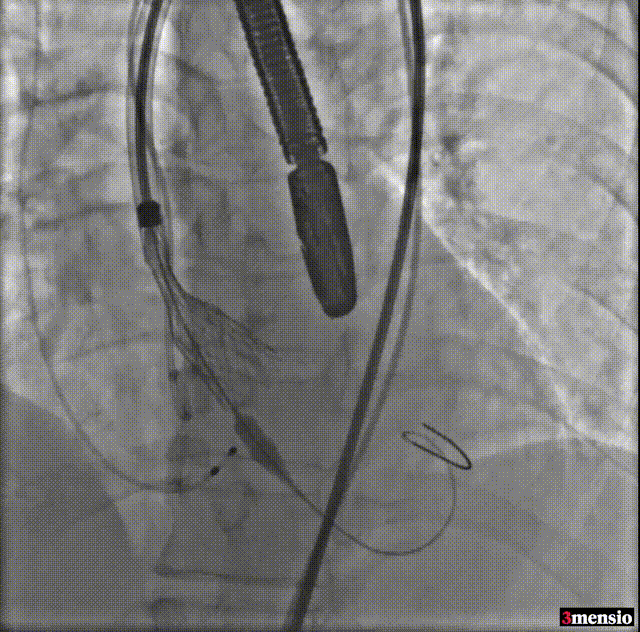

导丝跨瓣

球囊预扩

预释放定位

瓣膜释放至工作位

工作位造影

释放后造影

由于该病例瓣上限制较重,手术团队讨论决定使用沛嘉20mm球囊后扩处理:

球囊后扩

瓣膜最后形态造影

压差

术前压差:115mmHg

术后压差:9mmHg